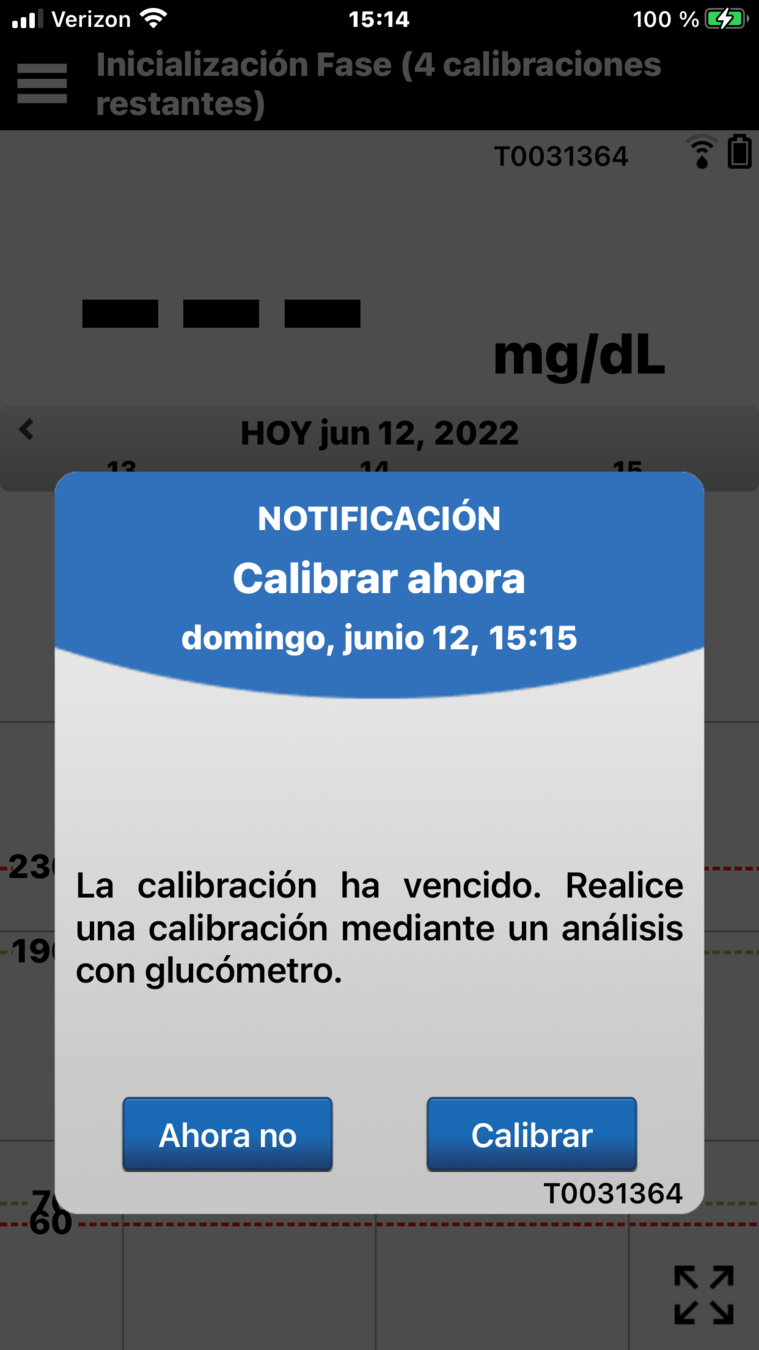

Ahora que ha colocado correctamente el transmisor inteligente Eversense® E3, verá en la aplicación móvil una notificación Calibrar ahora al cabo de unos minutos .

Esto quiere decir que es hora de realizar la primera de las 4 calibraciones mediante punción capilar.

No obstante, no tendrá que recordar el momento en el que tiene que realizar cada calibración, ya que el sistema de MCG Eversense® E3 se lo recordará con una notificación "Calibrar ahora".

Para introducir una calibración, haga una comprobación de glucosa en sangre mediante punción capilar…

… y toque en el botón Calibrar.